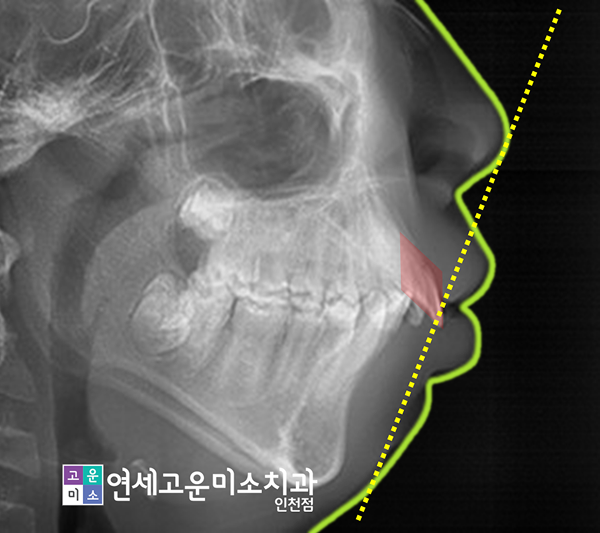

코 끝에서 아래턱 끝으로 이어지는 직선을 기준 삼아 입이 얼마나 나왔는지를 알 수 있다고 알려졌는데요.

상악이 약간 앞으로 나온 무턱 경향을 보이고 있으며, 윗니의 전방 경사로 인해 입술이 도드라져 보였습니다.

이런 경우에 돌출입 교정은 앞니를 뒤로 끌어당기는 후방이동을 통해 측면안모를 개선시킬 수가 있는데요.

위 사진에서도 볼 수 있듯이 아래턱이 약간 들어가면서 상대적으로 위턱이 더 나오는 양상을 보이고 있었습니다.

뿐만 아니라 발치교정으로 돌출입 교정이 진행됨에 따라 측면 안모가 바뀌었습니다.

윗니의 전방경사가 감소하고 치아를 뒤로 움직인 만큼, 입이 안쪽으로 들어간 결과를 확인해볼 수 있었습니다.